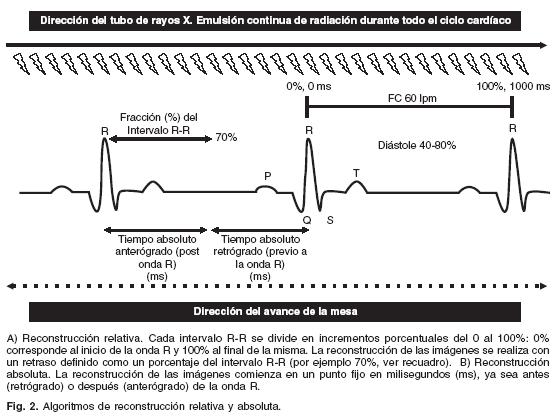

En los protocolos de reconstrucción retrospectiva se emite radiación durante la totalidad del ciclo cardíaco. En esta técnica, el avance lento de la mesa y por ende del paciente, está diseñado para solapar las rotaciones del gantry (interpolación– z) al mismo tiempo que se graba el trazo ECG del paciente, el cual se usa para enlazar posteriormente los datos adquiridos con fases particulares del ciclo cardíaco13 . Esta forma de reconstrucción facilita la obtención de imágenes en puntos del ciclo cardíaco donde existen menores probabilidades de artificios por movimiento, generalmente en diástole que es cuando menor movilidad cardíaca existe18–20. Cada nivel anatómico adquirido en el eje cráneo–caudal o eje z está representado en varios latidos cardíacos. Debido a que todo el ciclo cardíaco está representado, el operador puede escoger de manera retrospectiva, ya sea de forma anterógrada (después de la onda R) o retrógrada (antes de la onda R), cualquier parte del ciclo cardíaco para obtener una serie de imágenes reconstruidas en la misma fase del ciclo cardíaco. La selección del momento apropiado para la reconstrucción puede expresarse en mseg en relación a la onda R (reconstrucción absoluta), o seleccionarse un % del intervalo R–R al que se va a reconstruir (reconstrucción relativa)5,16 (Fig. 2). No existe un consenso sobre cuál es la mejor técnica, sin embargo, en la gran mayoría de los centros se prefiere una reconstrucción retrospectiva anterógrada relativa, esto es una adquisición con emisión de radiación durante todo el ciclo cardíaco, con una reconstrucción a partir de la onda R en un punto "X" del intervalo R–R que se encuentra dividido de manera porcentual. La principal ventaja de los algoritmos de adquisición retrospectiva, es que permite reconstrucciones en cualquier punto del ciclo cardíaco. Su principal desventaja es la mayor dosis de radiación recibida por el paciente.

En ambas técnicas de adquisición (prospectiva y retrospectiva) pueden emplearse algoritmos de reconstrucción sin utilizar una rotación de 360° del tubo de rayos–X, esto con el objetivo de incrementar la resolución temporal. Es decir, las imágenes se adquieren con la información de rotaciones parciales ("incompletas") de aproximadamente dos terceras partes de la rotación completa del tubo (240–260°).5,16,17 Esto mejora la resolución temporal a aproximadamente la mitad del tiempo de rotación del tubo de rayos–X: 250 mseg en el caso de un tiempo de rotación de 500 mseg, y de 165 mseg para un tiempo de rotación de 330 mseg. En el caso de los nuevos sistemas duales, la resolución temporal podría ser menor a los 100 mseg. Además, estos protocolos permiten incrementar el pitch (relación entre el avance de la mesa/colimación total del corte), y por ende disminuir el tiempo de adquisición y la radiación recibida por el paciente.4